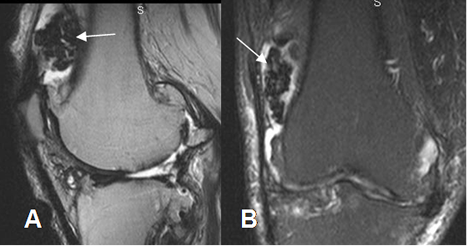

Fig 49. Sinovitis villonodular pigmentaria.

A: RM sagital en T2 y B: RM coronal en STIR. Signos de sinovitis, con proliferación sinovial suprapatelar. (Flechas). Las lesiones son hipointensas, por el contenido de hemosiderina y fibrosis.